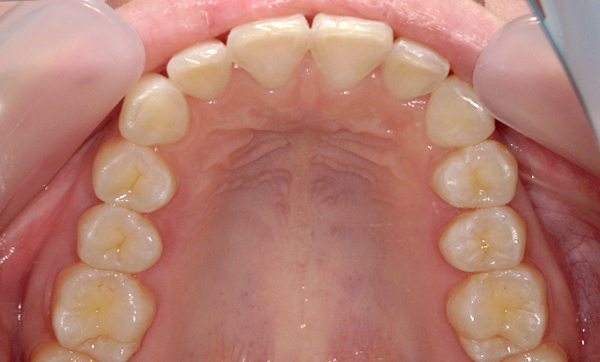

症例_008 「上下の前歯」症例

治療期間:13ヶ月金額:57万円+税40代女性捻転歯前歯のガタガタ

Before | After |

症例_008

治療リスク:後戻りの可能性